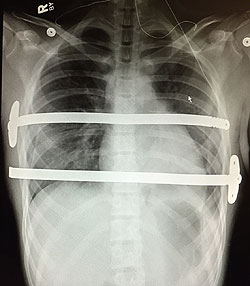

A CT scan confirmed his pectus excavatum diagnosis and revealed that John’s sternum was pushing into the right ventricle of his heart and displacing his heart to the left, explaining why he had been experiencing such pain and difficulty breathing. After thorough discussions with Dr. Alder and his assistant Cheryl, John and his family decided to move forward with surgery, where he would undergo what is known as the Nuss procedure. The minimally invasive procedure involves the insertion of a curved metal bar under the patient’s ribs and secured under the sternum to lift it upward. The bar is left in place for three years, allowing the chest to remold itself outward, and is then removed during outpatient surgery.